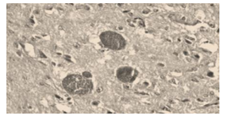

Na análise histopatológica abaixo, observam-se cistos contendo estruturas arredondadas compatíveis com protozoários. Esses parasitas estão associados a zoonoses relevantes e podem comprometer a qualidade sanitária de produtos de origem animal.